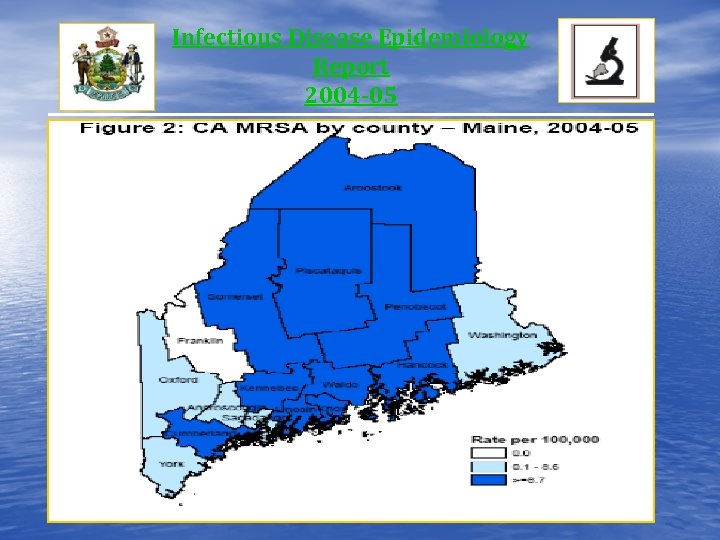

Infectious Disease Epidemiology Report 2004 -05

Infectious Disease Epidemiology Report 2004 -05